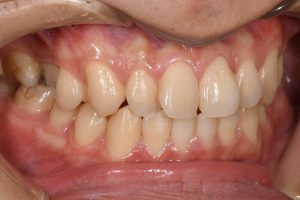

銀歯を全てセラミックにした症例

治療前

治療後

この患者様の場合

1回目にカウンセリング

2回目に型取り

3回目にセラミックのセット

の合計3回で治療終了となりました。